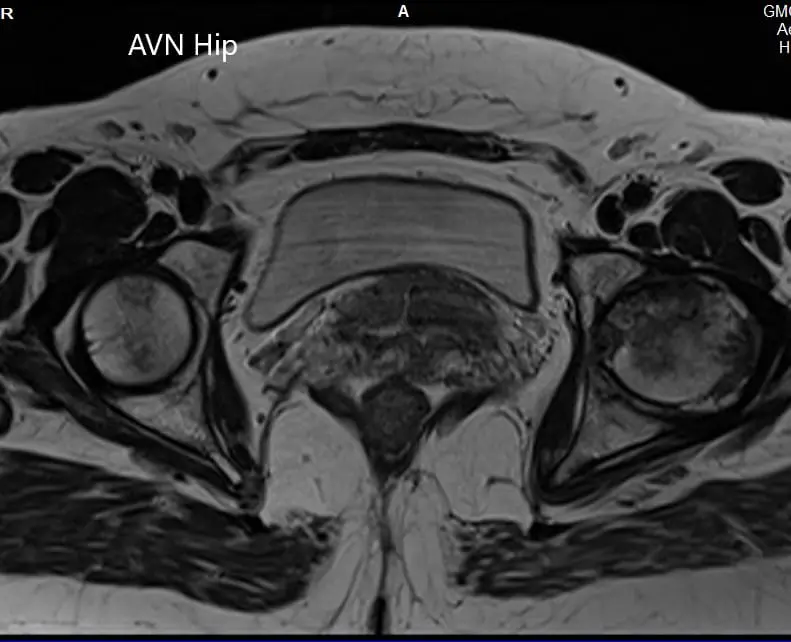

An MRI was obtained which showed altered signal intensity in both T1WI and T2WI. There was a subtle collapse of the left femoral head. A serpiginous hyperintense line was seen on T2WI demarcating an area of osteonecrosis in the left femoral head. This area involved the lateral and medial compartment and covered more than 50% of the surface area of the head.

Secondary osteoarthritic changes were visualized in the form of reduction of anterosuperior joint space and osteophyte formation. A small amount of fluid was seen in the joint cavity.

T1WI and T2WI of the MRI showing an axial section of the bilateral femoral head.